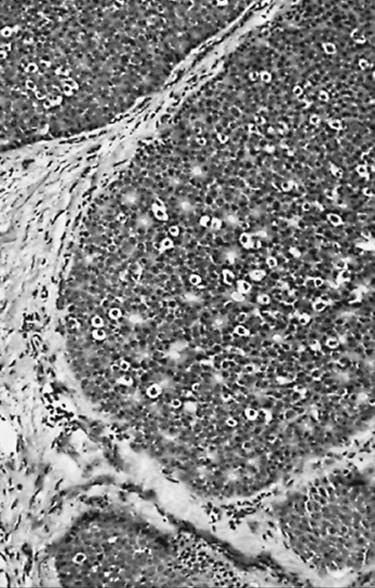

Microscopic examination shows that many follicles are small, the amount of colloid is decreased, and infiltrates of lymphocytes, plasma cells, and macrophages are extensive (Fig. 21.2) (70,71). Lymphoid follicular centers are numerous, and their antibody-producing B-cells are polyclonal; those containing IgG are the most numerous (59,60,61,68,72). T-cells are most frequent among the epithelial cells and in the interstitial tissue away from lymphoid follicles. In flammatory giant cells may be scattered through the damaged follicles; their presence should not lead the pathologist to mistake autoimmune thyroiditis for de Quervain's thyroiditis (71). The amount of connective tissue in the gland often increases. Some follicular cells appear atrophic or damaged; many are hyperplastic or metaplastic (oncocytic or Hürthle cells; squamous metaplasia) (73,74). The solid-cell nests have been suggested as the origin of the latter (21,74). Possibly related rare cystic lesions have also been noted (38,40,75,76).

FIGURE 21.2. Autoimmune thyroiditis. Lymphoid follicles are conspicuous. Only a few colloid-filled thyroid follicles remain; most of these follicles are small and were formed by hyperplastic and metaplastic cells.